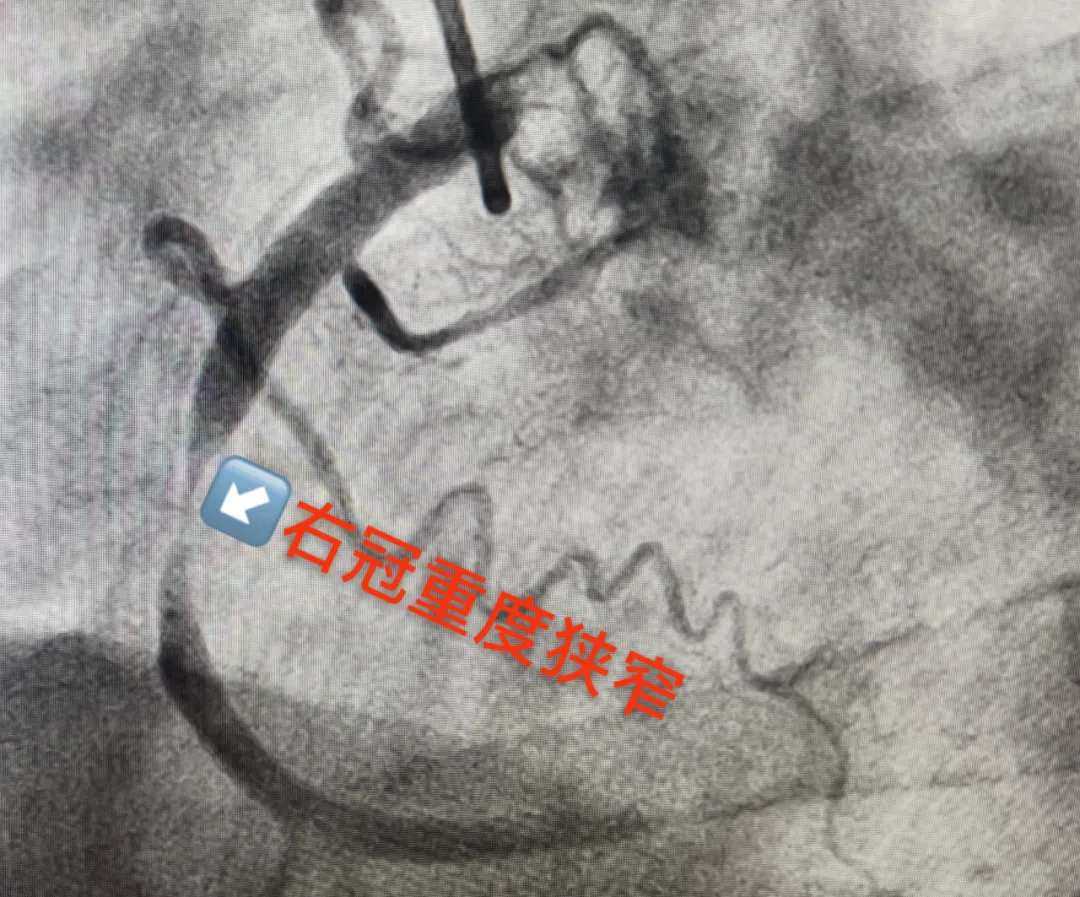

心内科团队接力:将造影导管送至冠状动脉开口,通过同一入路更换造影导管,造影剂注入瞬间,屏幕上清晰显示右冠状动脉中段一处近乎闭塞的狭窄–狭窄程度高达99%,如同心脏供血的“主干道”被掐住了喉咙!若不及时处理,随时可能引发急性心肌梗死甚至猝死。

“一站式”造影:冠脉重度狭窄+颅内动脉瘤现形

经与患者及家属充分沟通后,团队决定为患者实施“冠状动脉造影+脑血管造影”一站式检查。